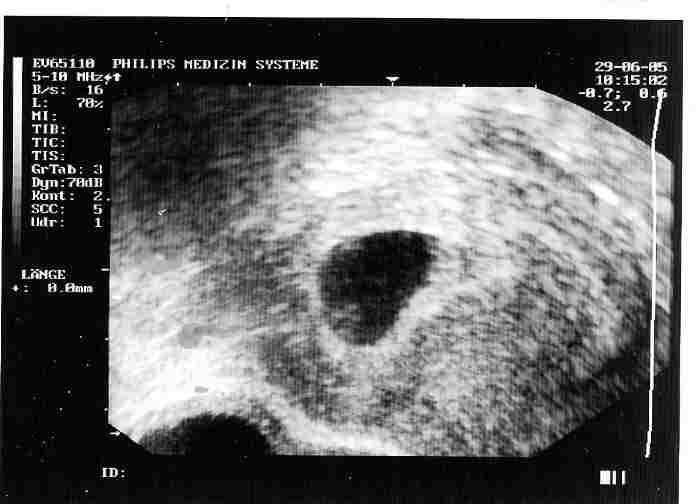

so, ich probier das jetzt mal mit dem US-Bild.... viel ist allerdings noch nicht zu sehen...

das weiße in der "ecke" ist unser zwerg. beim ersten mal 4mm groß, beim 2. mal (VU2) schon 10mm!!!